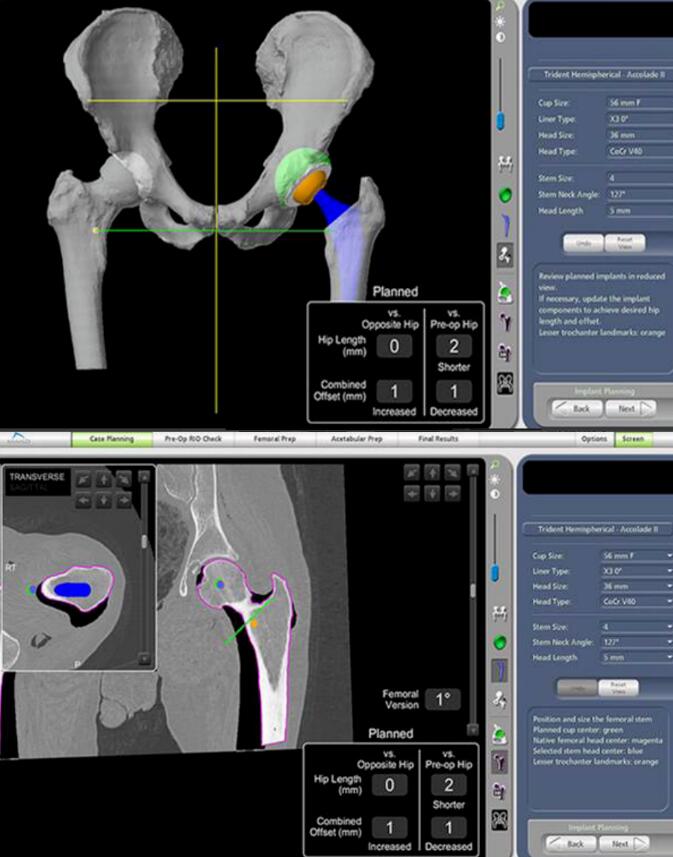

Mako智能机器人是一款基于智能手术规划技术和智能辅助截骨技术的关节手术机器人,系统囊括了临床诊断、术式设计、手术虚拟仿真、疗效评价、手术导航和远程医疗等。

机械臂、导航模块和摄像立架是Mako机器人的核心组成部分,它们犹如人的“手臂”、“大脑”和“眼睛”,将传统的手动手术过程转化为数字化规划,通过“术前完整的手术规划”、“术中1度和1毫米的精准截骨与假体植入”,实现人工关节的高精度植入,使其完美适配人体关节的生理结构与活动需求,达成“精准微创、加速康复”的治疗目标。

利用患者术前CT数据构建3D骨骼模型,通过导航模块在专属3D模型图像上规划植入物尺寸与摆放位置,对安装效果和截骨量、截骨角度等进行提前“预演”,实现精准术前方案定制。

2、术中:实时动态平衡与智能防错

手术中系统实时捕捉软组织张力,关节面的接触点,髋关节的前倾角,下肢长度,旋转中心,偏心距等临床信息,医生据此调整手术计划,实现关节平衡并达到1度1毫米个性化放置。当操作偏离预设路径0.1毫米,机械臂触发阻力反馈、警报并终止操作。